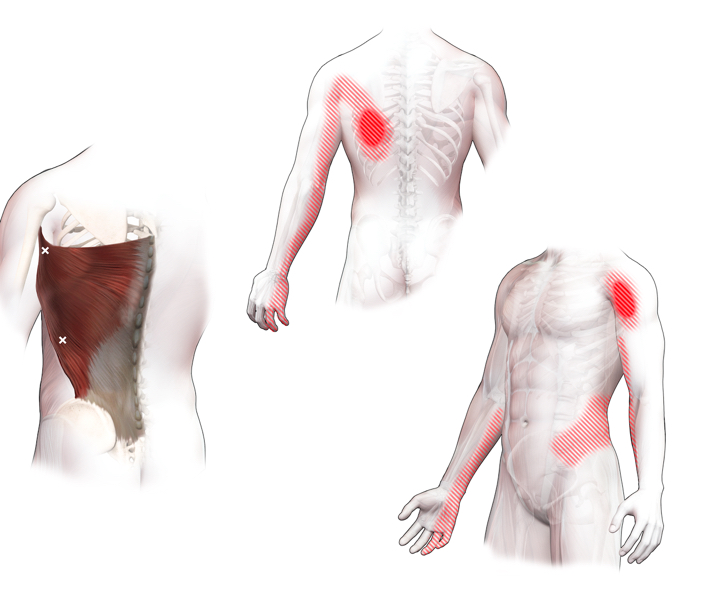

Spieren (Nederlands)

Spieren (nederlands)

Spieren (Latijn)

Spieren (latijn)